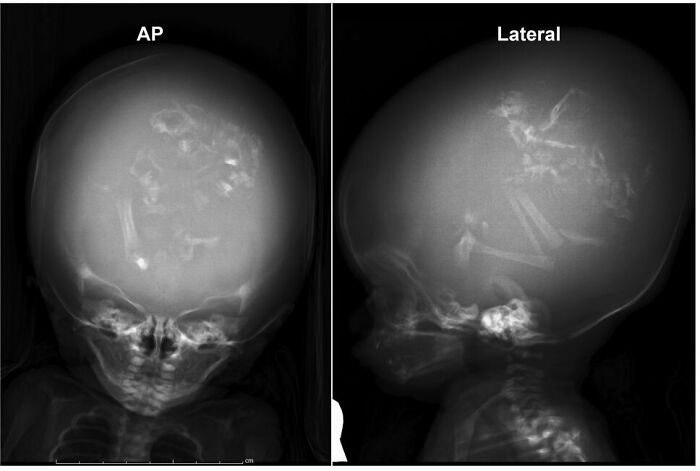

Antes y después de una operación de duplicación craneofacial